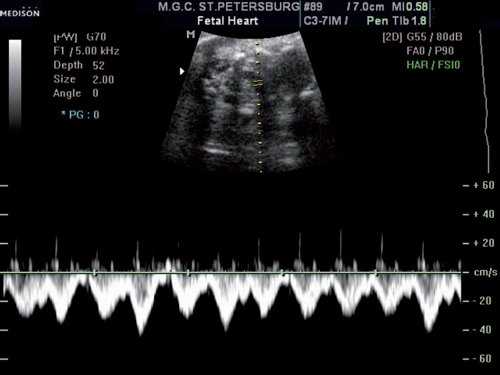

При исследовании в режиме ЦДК сохранялось направление тока крови слева направо (рис. 3), при исследовании в режиме импульсного допплера спектр кровотока в этом сосуде соответствовал двухфазному спектру кровотока в венах, располагающихся близко к сердцу (рис. 4). Учитывая направление и спектр тока крови в сосуде, был сделан вывод, что данный сосуд представляет собой левую безымянную (плечеголовную) вену.

Рис. 4. Оценка характера кровотока в исследуемом сосуде в режиме импульсного допплера. Спектр кровотока двухфазный, типичный для вен, располагающихся близко к сердцу.